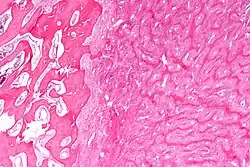

Micrograph showing fibrous dysplasia with the characteristic thin, irregular bony trabeculae and fibrotic marrow space. H&E stain.

Micrograph of fibrous dysplasia (right) juxtaposed with unaffected bone (left). H&E stain.

Fibrous dysplasia is a mosaic disease resulting from post-zygotic activating mutations of the GNAS locus at 20q13.2-q13.3, which codes for the α subunit of the Gs G protein-coupled receptor.[13] In bone, constitutive Gsα signaling results in impaired differentiation and proliferation of bone marrow stromal cells.[14] Proliferation of these cells causes replacement of normal bone and marrow with fibrous tissue. The bony trabeculae are abnormally thin and irregular (bony spicules on biopsy).